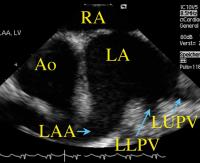

Figure 3: Left atrium, left atrial appendage, and left pulmonary veins demonstrated with the AcuNav(TM)-catheter being placed in the right atrium and lined up with the interatrial septum. Ao = aorta; LAA = left atrial appendage; LA = left atrium; LLPV = left lower pulmonary vein; LUPV = left upper pulmonary vein; RA = right atrium

Keywords: Arteria pulmonalisArteria pulmonalisAtriumAtriumCatheterechocardiographyEchokardiographieKatheter